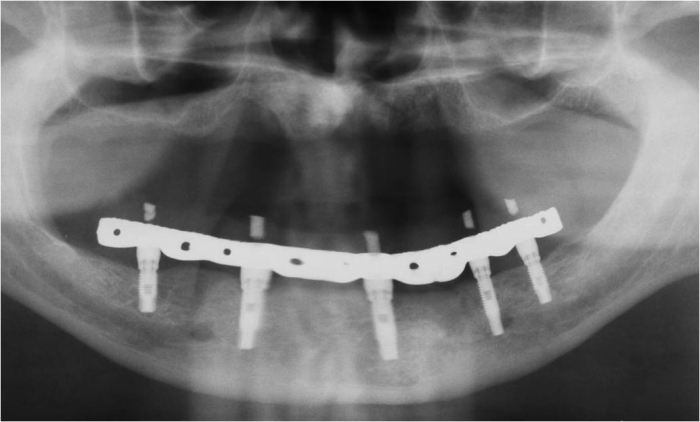

Raio X final